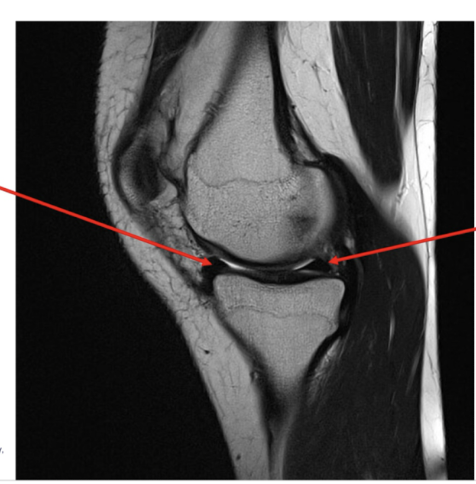

51

New cards

Pathology

• Medial collateral ligament tear

• High signal intensity within the

medial aspect of the knee indicative of fluid presence as a result of a pathological process in this case the tear.

Sequence + pathology?

• 1st = PD: intermediate signal from muscle and fat is bright, image quality is much better

• 2nd = PD FS: fat has been supressed appearing much darker

• Path = complete ACL tear: in a normal knee you would see a black band which is the acl sitting

across the anterior aspect of the tibia and extending to the posterior aspect on the femur. This is not present at all hence, a tear.